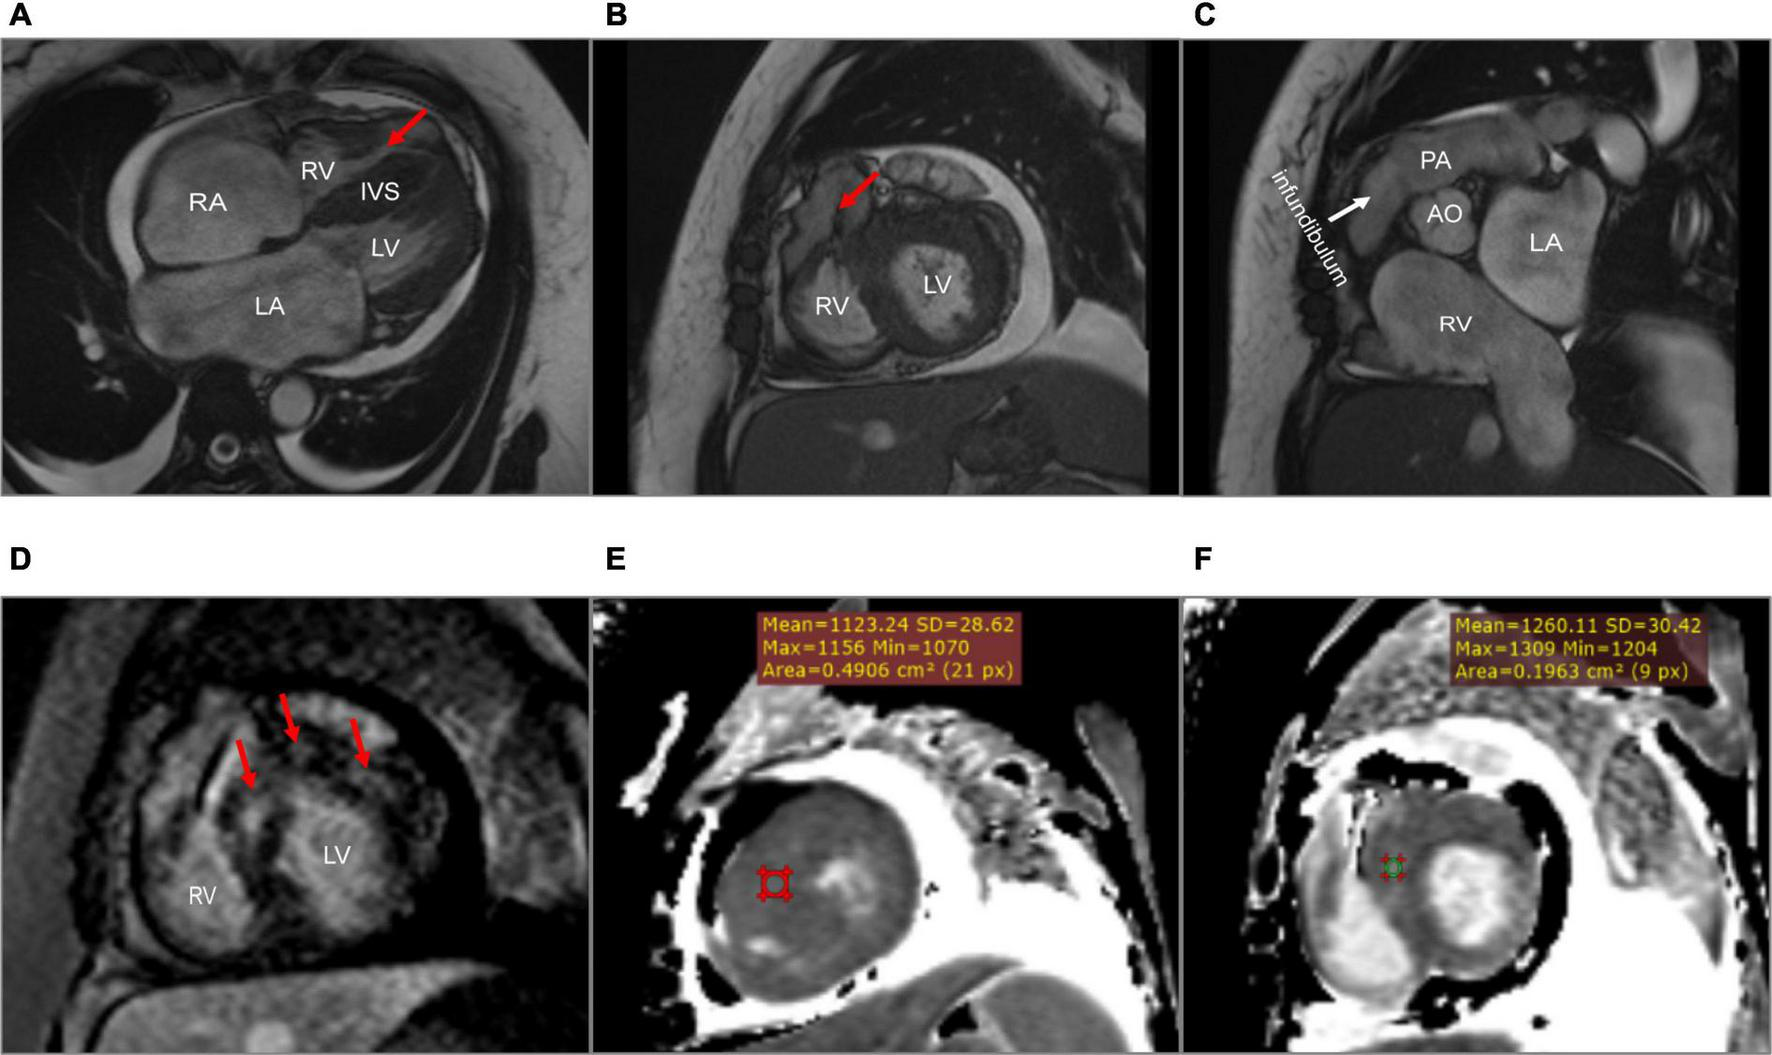

A 45-year-old woman presenting with a 10-year history of palpitations and recent aggravation accompanied with dyspnea was referred to our center. She was originally diagnosed with biventricular HCM yet did not receive relevant treatment. Assessment of family medical history revealed that her mother died of a sudden cardiac death (SCD). Upon physical examination, the patient’s vital signs were stable, with the exception of tachycardia (112 beats/min) and a loud grade 4/6 systolic ejection murmur in the 4th intercostal space along the left sternal border. Routine 12-lead electrocardiography displayed recurrent AFL at a ventricular rate of 112 beats/min (Figure 1A). Transthoracic echocardiography (TTE) revealed mildly reduced left ventricular ejection fraction (EF: 45%), mild pericardial effusion, biatrial enlargement (left atrium: 54 mm × 68 mm × 58 mm; right atrium: 59 mm × 43 mm) (Figure 2A), biventricular hypertrophy and asymmetrical interventricular septal hypertrophy (20 mm) (Figure 2B). The anomalous muscle bundles inferior to the infundibulum divided the RV into two cavities, inducing right ventricular outflow tract (RVOT) obstruction (Figures 2C,D and Supplementary Videos 1, 2). The peak pressure gradient of RVOT was approximately 44 mmHg, and the forward flow velocity was measured at 333 cm/s (Figure 2E). The obstructive gradient, however, may have been underestimated due to the inability of color Doppler to align turbulent flow. Furthermore, a small left to right membranous ventricular septal defect (VSD) (0.3 cm) shunt was discovered in the high-pressure chamber (Figure 2F and Supplementary Video 3). Cardiac magnetic resonance (CMR) further confirmed the presence of sub-infundibular obstruction, biventricular hypertrophy, and interventricular septal hypertrophy (basal segment: 22.5 mm, middle segment: 25.5 mm, distal segment: 21 mm). A dumbbell-shaped RV and flow acceleration at the RVOT were observed during systole (Figures 3A,B and Supplementary Video 4). CMR assessed RV function with a right ventricular ejection fraction of 63%, right ventricular end-diastolic volume of 61 ml, and right ventricular end-systolic volume of 23 ml. No signs of stenosis were identified in the infundibulum, PV, and pulmonary artery (PA) (Figure 3C). Scattered patchy late gadolinium enhancement (LGE) was seen within the left ventricular myocardium, particularly in the left ventricular anterior wall and interventricular septum (Figure 3D). The native T1 mapping revealed a markedly increased T1 value at basal IVS from 1,123 to 1,260 ms (Figures 3E,F). The reference native T1 value of our 1.5T scanner was 1,035 ms. Genetic testing detected one HCM-associated mutation: MYH7, c.4135G > A, p. Ala1379Thr. MYH7 is the most frequent pathogenic gene of HCM, accounting for 40–44% of HCM cases (3).

FIGURE 3

Cardiac magnetic resonance. (A) A dumbbell-shaped right ventricle indicated right ventricular outflow tract obstruction (the red arrow). (B) A flow void sign at the right ventricular outflow tract (the red arrow). (C) No stenosis of infundibulum, pulmonary valve, and pulmonary artery. (D) Scattered patchy late gadolinium enhancement within the left ventricular myocardium (red arrows), particularly in the left ventricular anterior wall and the interventricular septum. (E,F) The native T1 mapping revealed the markedly increased T1 value at the basal interventricular septum from 1,123 to 1,260 ms. LA, left atrium; RA, right atrium; LV, left ventricle; RV, right ventricle; IVS, interventricular septum; PA, pulmonary artery; AO, aorta.